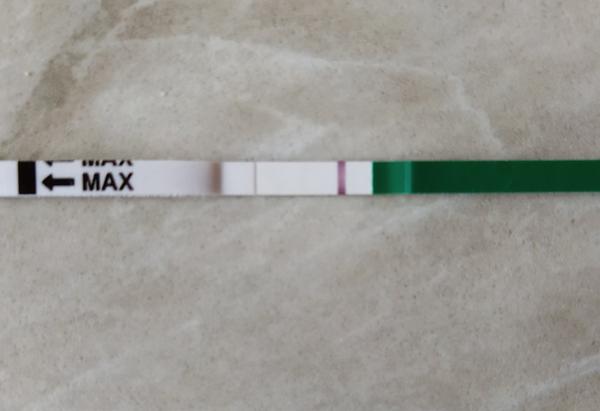

ahojte babule, mam taku otazku...mate skusenost ze pocas 3 dni vam nesilnela druha ciarka na teste ale bola rovnaka???ako duch????

Ahojte baby potrebujem radu dnes som 9-10dpo, od včera mi je zle na žalúdku, vracala som, aj dnes mi je tak isto, tak je mi cudne... A test som si spravila až teraz poobede a nič tam špeciálne nevidím vy áno? Viem ze je to skoro, ale nedalo mi tak som si test spravila a zatiaľ tam nič nie je iba taky ako duch alebo len kanálik 🤔 neviem ťažko povedať..

@tinadeville no tebe to vidno pekne, ja som to mala takto isto voľným okom to lepšie bolo vidno